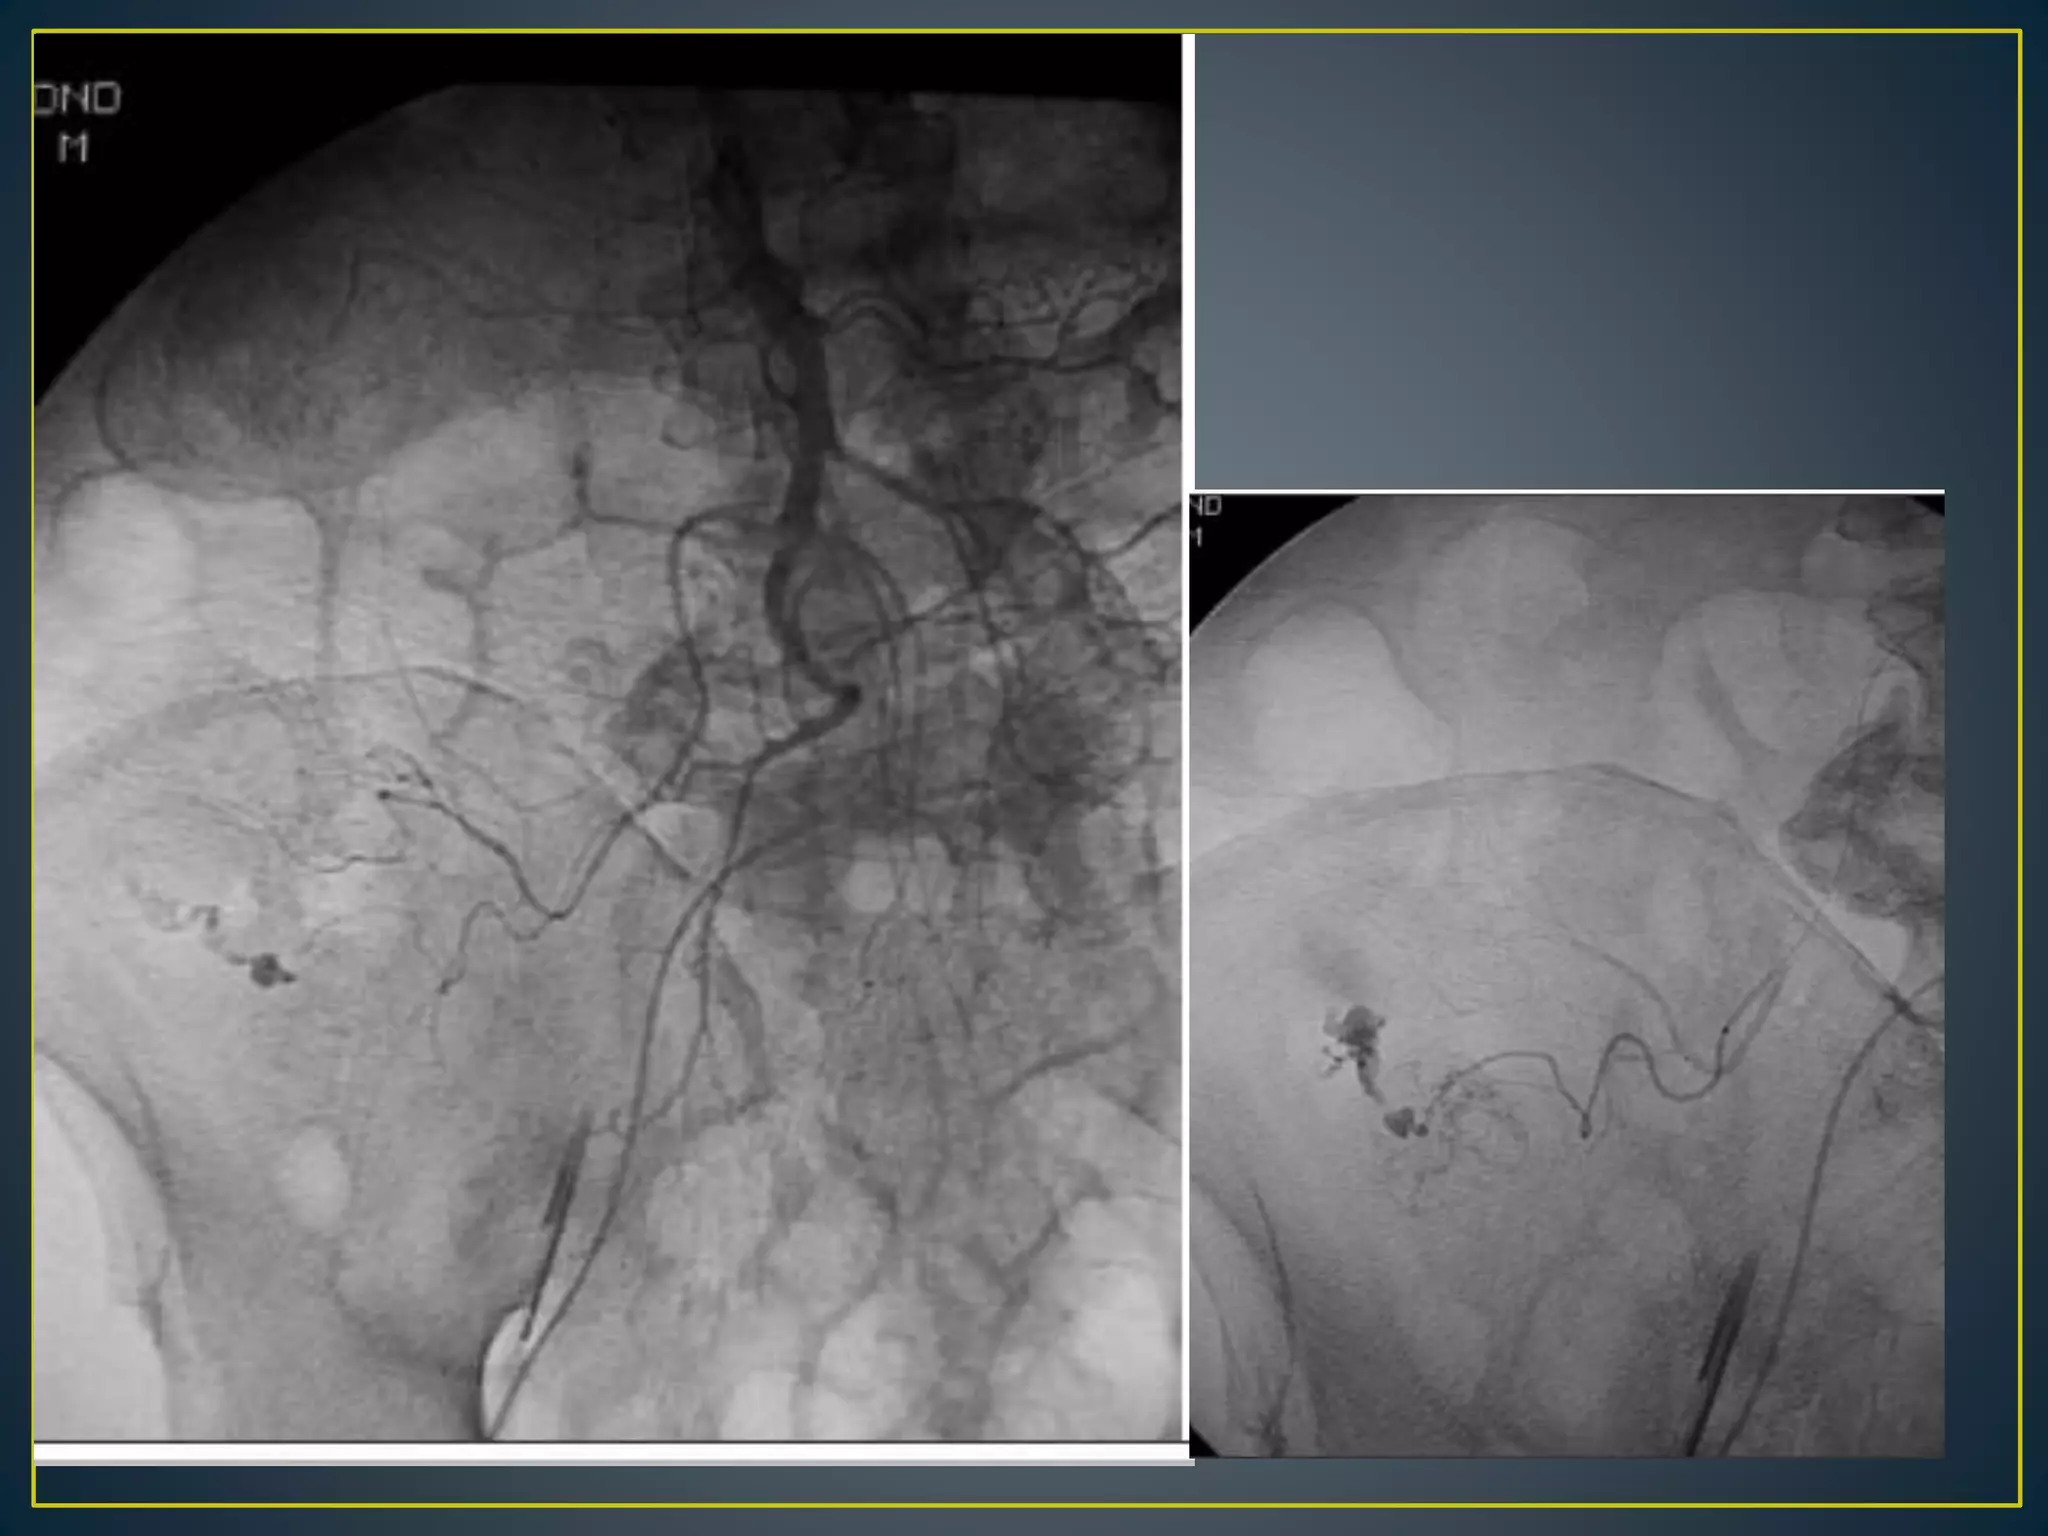

• Arteriovenous malformations located in the cecum and

ascending colonLesion affecting elderly persons older

than 60 years

• Composed of clusters of dilated vessels, mostly veins, in

the colonic mucosa and submucosa

• Colonic angiodysplasias are believed to occur as a result

of chronic, intermittent, low-grade obstruction of

submucosal veins as they penetrate the muscular layer

of the colon

• Angiodysplasia tends to cause slow but repeated

episodes of bleeding

• Angiodysplasias can be easily recognized by

colonoscopy as 1.5- to 2-mm red patches in the mucosa

• Angiodysplasia is diagnosed by early and then

persistent filling of a draining vein and by an abnormal

cluster of vessels in the bowel wall

• Lesions can be multiple. The abnormality is identified by

early venous drainage from one portion of the bowel or

a "tram track" sign from simultaneous opacification of the

feeding artery and draining vein.

• Contrast extravasation usually is not seen. Because

angiodysplasia is relatively common in elderly patients

and may be an incidental finding, other sources of

bleeding should be considered.